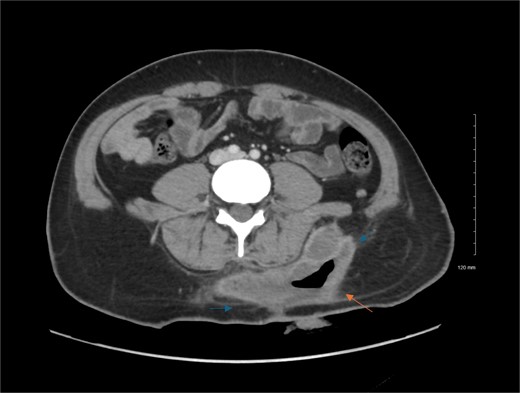

At the time of the presentation, the patient looked well, in mild pain but not in distress, vitally and clinically stable. Upon examination, there were two right gluteal incisions, measuring 15 cm and the lateral incision measuring 3 cm. The area was swollen, surrounded by erythema and fluctuant, mildly tender to touch. Laboratory findings were unremarkable. With the patient’s presentation, we proceeded with CT scan that showed infected gluteal hematoma (Fig. 1).

Contrast enhanced axial CT scan of the abdomen. Contrast enhanced CT scan of the abdomen shows left lower back fluid collection with peripheral thick wall enhancement (blue arrows), consistent infected collection. There is also air seen within the collection (orange arrow), indicating prior attempted evacuation.